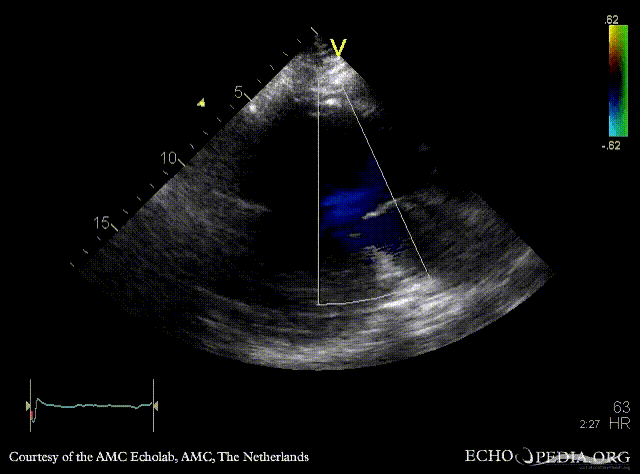

PLAX: large pseudoaneurysm of posterior wall PLAX: Color Doppler, severe mitral regurgitation